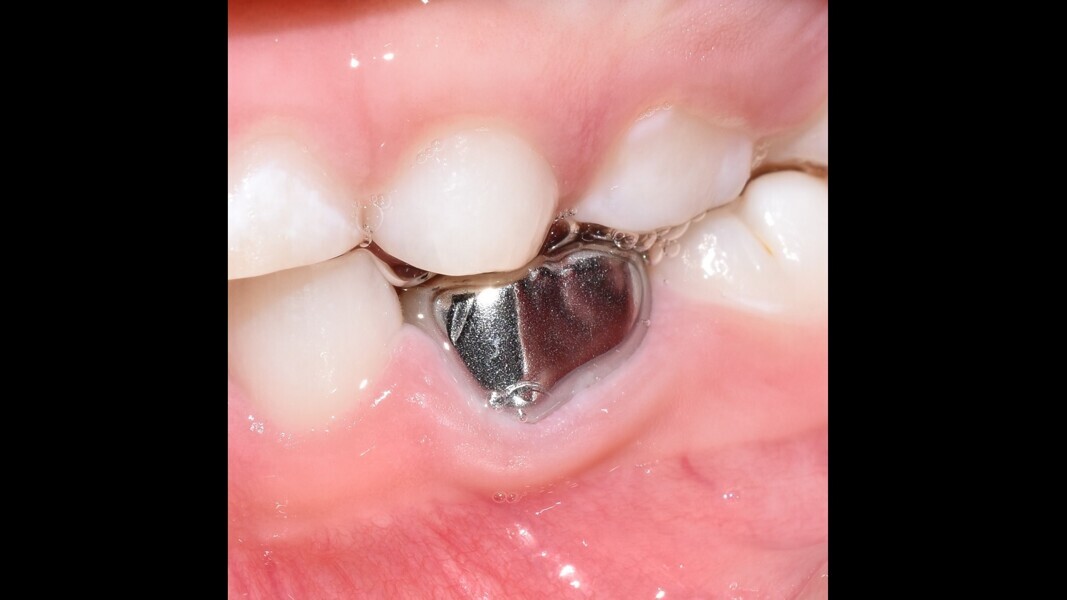

• At a second appointment, 15 days later, upon confirming the absence of signs or symptoms of disease, a stainless-steel crown was adapted and cemented with glass ionomer in a powder–liquid form (Ketac Cem Easymix).

This male patient was 6 years and 7 months old and presented with severe tooth decay on the mandibular left first primary molar without any symptoms of pain. He experienced slight discomfort to percussion and palpation of the buccal gingiva. A buccal abscess and no mobility were observed. The radiograph showed a large area of interradicular bone loss. The tooth was diagnosed with pulp necrosis and an asymptomatic apical abscess. Pulpectomy was performed, and at a second appointment, a stainless-steel crown was placed upon confirming absence of signs or symptoms of disease. At the 14-month recall, no clinical pathology was detected and a normal eruptive process of the permanent premolars was observed in spite of the extrusion of the obturation material.